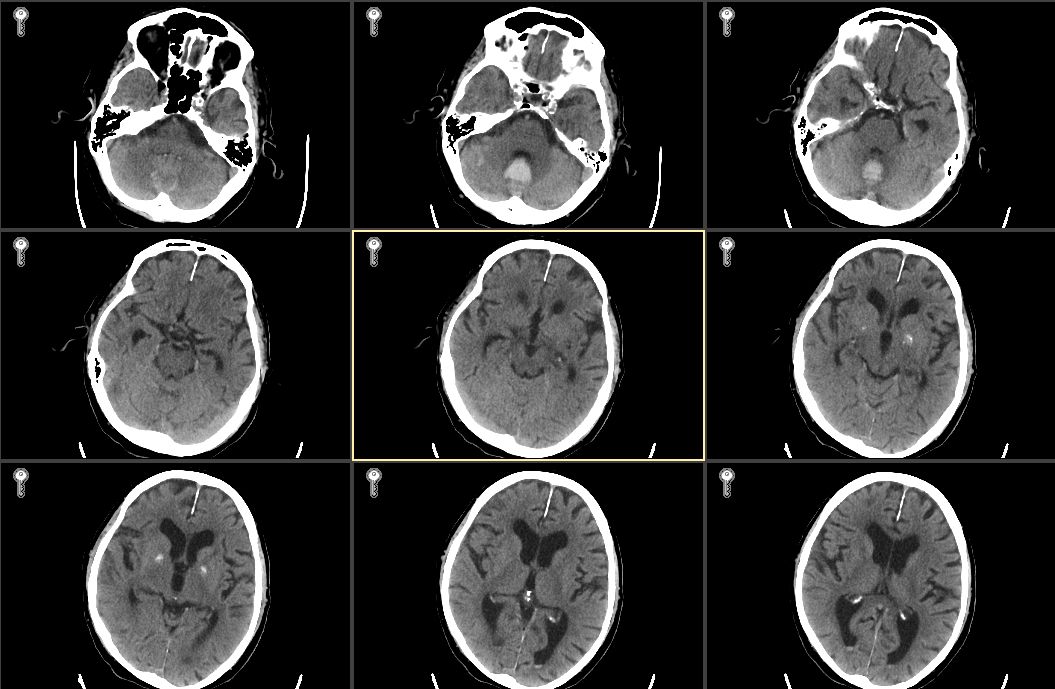

1 资料与方法病例1,男性,87岁,因“洗澡后突发头痛,呕吐半天”急诊入院。既往史有高血压病史数十年,血压控制良好;冠心病史,2007年接受“冠脉搭桥术”,长期服用拜阿司匹林325 mg 1次/d,辛伐他汀80 mg 1次/晚。入院查体:格拉斯哥昏迷评分法(Glasgow Coma Scale,GCS)14分,双瞳等大等圆,光敏,四肢肌力正常,双侧病理征阴性。入院头颅CT(图 1)示小脑蚓部血肿,量约7 mL,四脑室和环池清晰;双侧额顶叶,脑室旁多发缺血腔隙灶,脑萎缩。CTA提示未见明显异常。

| 图 1 2007年5月11日患者入院第1天头颅CT |